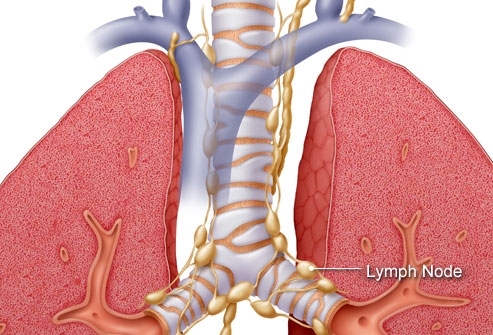

Mỗi loại ung thư phổi có cách xâm lấn khác nhau trong cơ thể. Như ung thư phổi tế bào nhỏ được chia thành hai giai đoạn: Giai đoạn giới hạn có nghĩa là ung thư được giới hạn trong một phổi và các hạch bạch huyết có thể ở gần vị trí khối u. Giai đoạn ung thư lan rộng có nghĩa là ung thư đã lan rộng khắp phổi hoặc ra các bộ phận khác. Ung thư phổi không phải tế bào nhỏ được chia thành từ 1 đến 4 giai đoạn, tùy thuộc vào việc khối u lan rộng đến đâu.